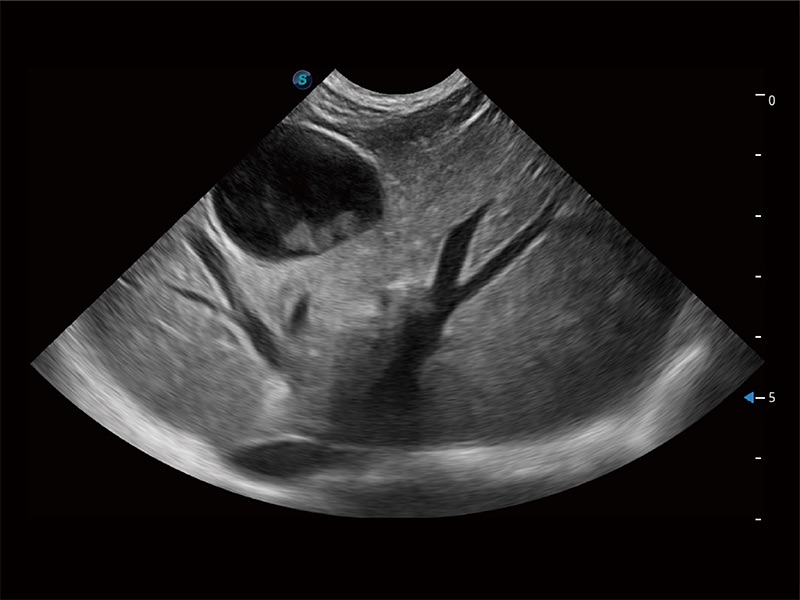

高性能和先进的临床应用工具可以为动物医生提供临床信心。ProPet 80 搭载了先进的腹部和浅表应用工具,帮助医生在日常临床实践中发挥前所未有的作用。

ProPet 80 配备了丰富的心脏探头群、先进的成像技术和专业的心脏测量工具,可帮助动物医生为不同体型和生理结构的动物提供心脏和心肌功能的全面评估。

ProPet 80 专为动物医生设计,对不同的动物体型和生理结构作出了针对性的优化。通过动物影像专用软件,可满足个性化的应用需求,帮助动物医生获得更精确的诊断数据。

ProPet 80 全新的动物超声智能软件和丰富的探头群,为动物医生提供了高清晰度和精细分辨率的图像,无论在宠物、马科、畜牧还是实验室动物等应用中都可以轻松应对,为您的日常工作带来满意的体验。